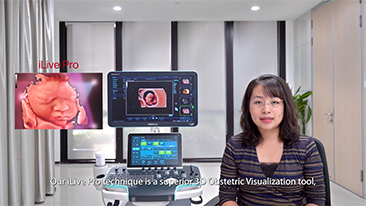

? necessĂĄrio otimizar fluxos de trabalho de obstetrĂcia e ginecologia para suportar grandes volumes na triagem da saĂșde da mulher. Por exemplo, as mĂĄs-forma??es do sistema nervoso central (SNC) s?o uma das anomalias congĂȘnitas mais comuns. Obten??o de imagens ruins devido Ă mĂĄ posi??o fetal, o MSP Ă© particularmente difĂcil de ser encontrado em um ultrassom 2D. Portanto, a detec??o e as medi??es automĂĄticas podem aumentar muito a eficiĂȘncia da realiza??o do exame.